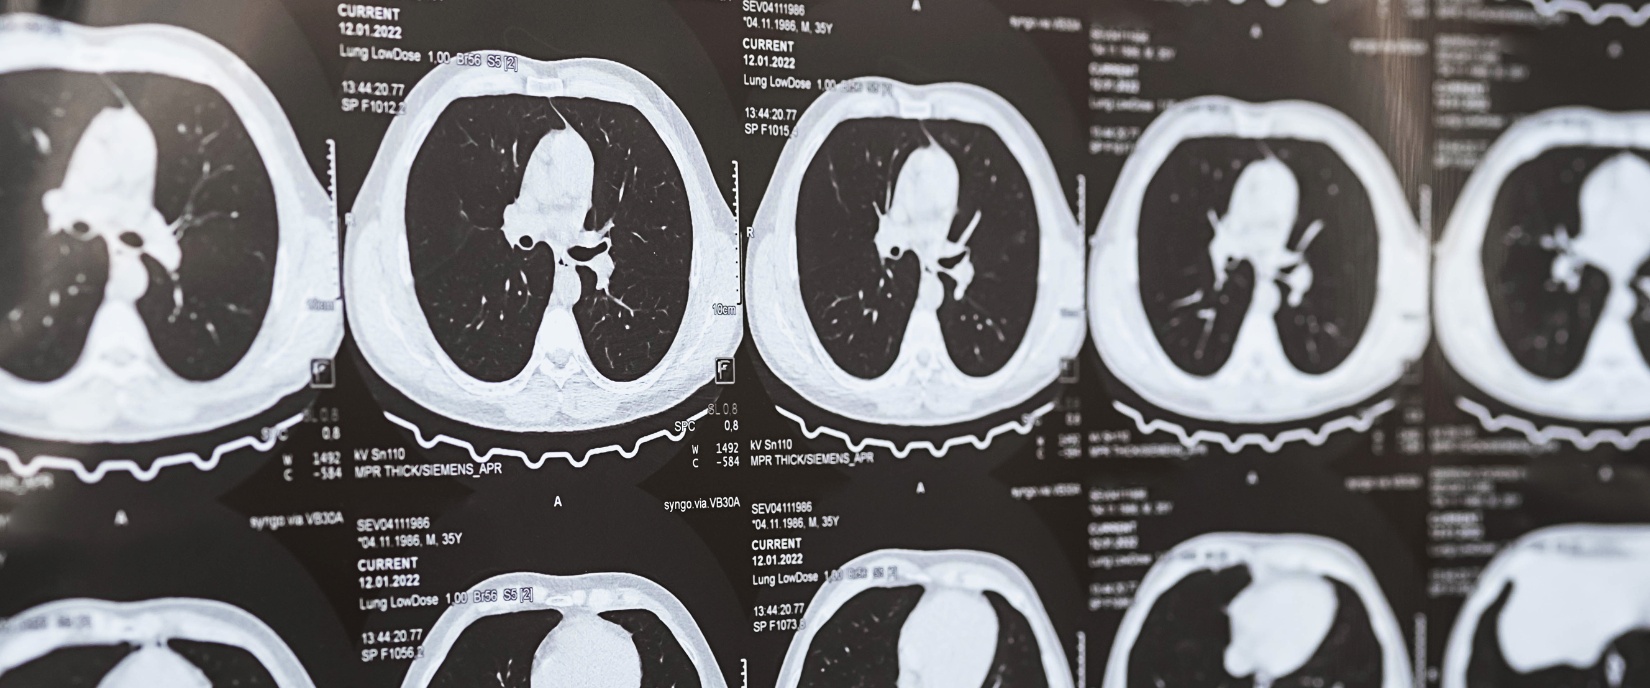

Low-Dose Lung Cancer Screening

You’ve heard it said often, but screening truly does have the potential to save lives, and our low-dose CT screening program available at East Alabama Health provides a way to detect lung cancer early in high-risk patients. A CT scan uses X-rays to make detailed images of your body. Unlike a standard X-ray that takes one picture, a CT scan rotates and takes images from many different angles. When a low-dose CT scan of the chest is done for lung cancer screening, it’s common to find small, abnormal areas (called nodules or masses) in the lungs, especially in current or former smokers. Most lung nodules seen on CT scans are not cancer. They are more often the result of old infections, scar tissue, or other causes. But tests are often needed to be sure a nodule is not cancer.

Board-certified radiologist Justin Phillpott, M.D. explains that low-dose CT scans are important because they could potentially detect lung cancer early, which could save lives. “Several studies have come out in the past 10 years proving that low-dose (meaning low radiation dose) CT scans performed on high-risk patients might detect cancers that could otherwise have been missed,” Dr. Phillpott explains. “Until now, the only cancer screening available in radiology was a mammogram.”